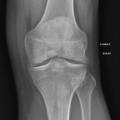

La forme pseudorhumatoïde est rare (5 %), simulant une polyarthrite rhumatoïde. L’arthrite chronique à PPC se présente comme une oligo- ou une polyarthrite, avec parfois des signes systémiques d’inflammation (élévation de la vitesse de sédimentation et de la protéine C-réactive [CRP]). La superposition d’accès aigus microcristallins est évocatrice de ce diagnostic. Il s’agit d’un diagnostic différentiel de polyarthrite rhumatoïde du sujet âgé ou de pseudopolyarthrite rhizomélique. Le diagnostic repose sur la mise en évidence des cristaux de PPC, même si les radiographies standard sont évocatrices. L’atteinte radiographique associe des calcifications des cartilages articulaires (fig. 7) et des fibrocartilages (fig. 8, 9, 10 et 11) [à rechercher systématiquement sur les radiographies de poignets, genoux et symphyse pubienne]. La mise en évidence d’une chondrocalcinose sur des radiographies standard renforce le diagnostic de rhumatisme à PPC mais l’absence de dépôts calciques ne l’élimine pas (la sensibilité de la radiographie standard étant imparfaite). L’échographie peut mettre en évidence des dépôts de PPC, qui apparaissent comme une fine bande hyperéchogène au sein des cartilages hyalins et comme des points scintillants dans les fibrocartilages ou dans la membrane synoviale. La sensibilité de l’échographie est bien supérieure à celle de la radiographie standard. Le scanner peut également mettre en évidence des dépôts calciques évocateurs, notamment au niveau du rachis ou du bassin qui sont plus difficilement explorés par les radiographies et l’échographie.

Les arthropathies liées à l’arthrose ou destructrices ont une fréquence qui augmente avec l’âge. L’arthrose associée aux dépôts de PPC touche en particulier les genoux, avec une symptomatologie chronique et/ou des accès aigus cristallins. Par comparaison avec l’arthrose idiopathique, l’arthrose avec dépôt de PPC serait à l’origine d’une symptomatologie plus inflammatoire, toucherait des articulations inhabituelles (radiocarpienne, carpienne, gléno-humérale, médio-pied et arrière-pied, cheville) et serait associée à plus d’ostéophytes et de géodes. Cette arthropathie dégénérative peut s’accompagner de lésions structurales sévères avec disparition rapide de l’interligne (arthropathies destructrices : hanches, genoux, poignets, coudes) mimant une ostéo­arthropathie nerveuse.